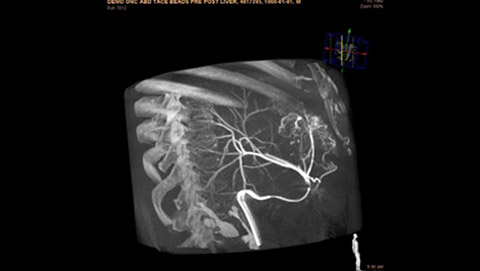

Dynamic 3D Roadmap provides a sustainable 3D roadmap to support interventional procedures. Dynamic 3D Roadmap matches the real-time 2D fluoroscopy images with the 3D-RA reconstruction of the vessel tree. It provides a 3D real-time insight of the advancement of the guide wire, catheter and coils through complex vessel structures. The Unsubtracted 3D Roadmap option reduces subtraction artifacts caused by patient breathing and movements, providing a clear roadmap during abdominal and thoracic interventions.